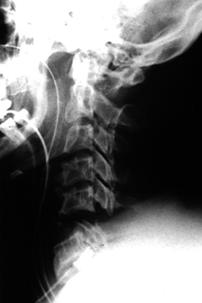

TRAUMA CERVICALA

Incidenta oblica Incidenta laterala Incidenta antero-posterioara

Aspect normal Aspect normal Aspect normal

Incidenta laterala Fractura Clay-Shoveler Luxatie atlanto-occipitala si

atlanto-axiala

Fractura de odontoida Fractura de odontoida si Luxatie atlanto-axiala

luxatie atlanto-axiala